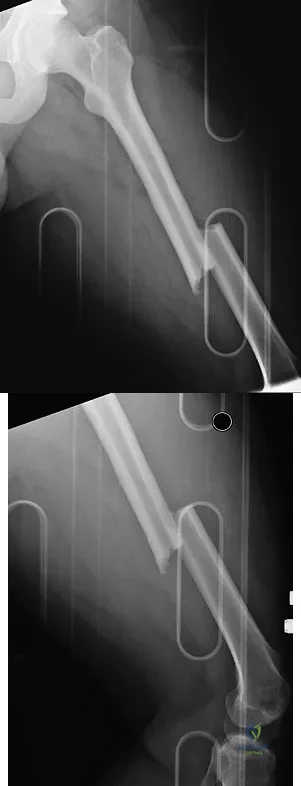

A 24-year-old man was thrown from a car and is seen in the emergency department with a Glasgow Coma Scale (GCS) score of 8. A CT scan of the head shows no significant bleeding. The patient is hemodynamically stable. The left femur has the closed injury shown on the radiographs in Figures 53a and 53b. What is the best treatment for this patient?

A 25-year-old male polytrauma patient undergoes initial temporary external fixation for a femoral shaft fracture. He is converted to a femoral nail at 7 days. This management can be expected to result in